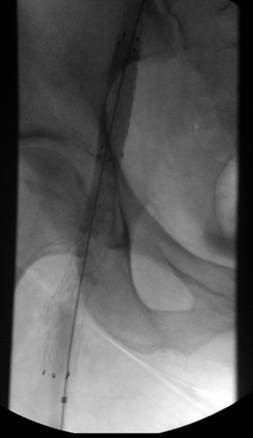

Paciente de sexo femenino de 35 años de edad con sarcoma endometrial metastásico y la pierna izquierda muy hinchada.

Pierna izquierda muy hinchada, a pesar de llevar medias de compresión de clase 2 hasta la altura del muslo. Obsérvese la bolsa del catéter de drenaje para nefrostomía.